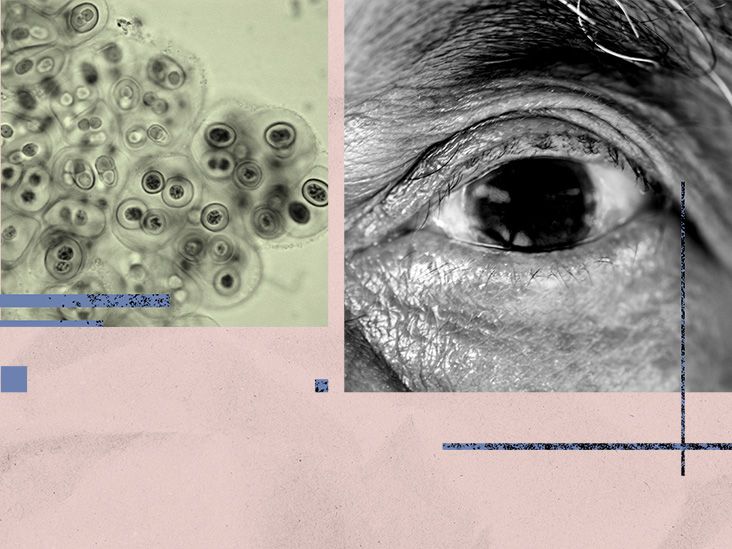

Common bacteria found in eye linked to increased risk

- A new study found that a common type of bacteria that causes sinus infections may stay in the eye for many years, potentially increasing a person’s risk for developing Alzheimer’s disease.

For this study, researchers examined retinal tissue from 104 people ranging from healthy cognition to mild cognitive impairment, to Alzheimer’s disease. Scientists used protein analysis, genetic testing, and advanced imaging to search for levels of the bacteria

Researchers discovered that retinal tissue samples from people with Alzheimer’s disease had significantly higher levels of Chlamydia pneumoniae, when compared to those with healthy cognition. Scientists also found that the higher the bacterial level, the more severe the cognitive decline.